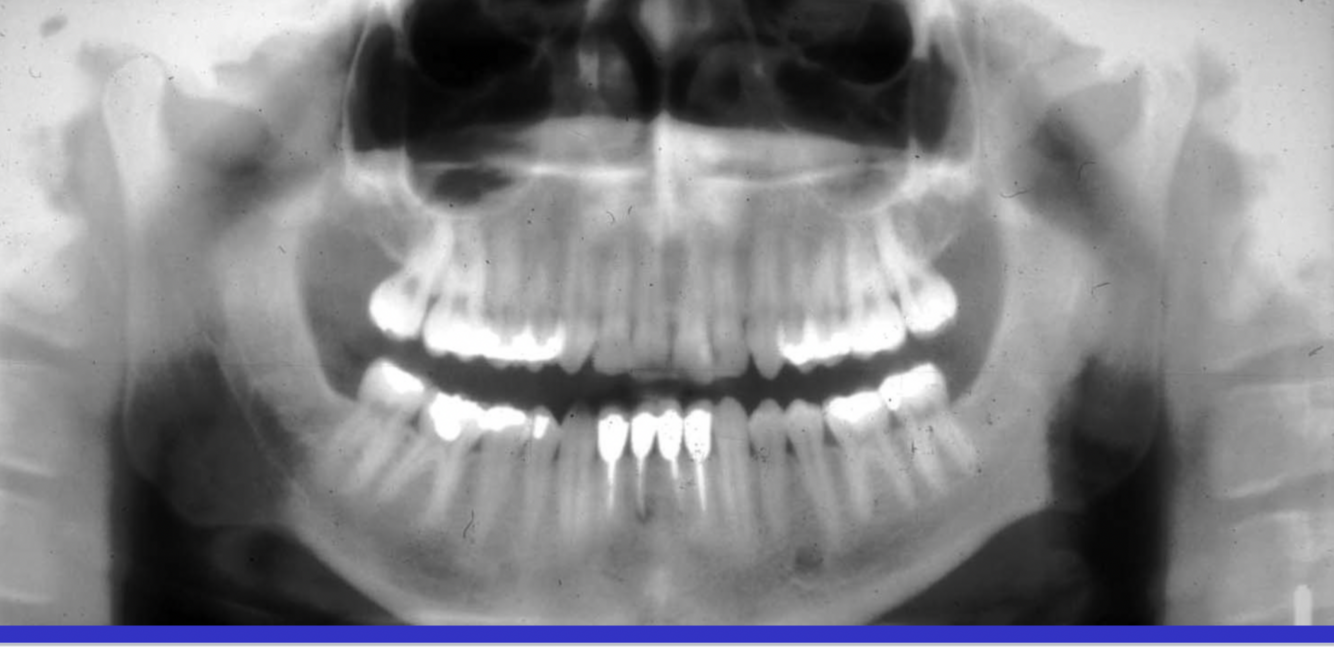

What errors can be seen in the following radiograph? What is the cause of these errors?

A

1. anterior teeth are narrowed & blurred

2. cervical spine is superimposed on ramus (double real image of cervical spine

Cause: too far forward